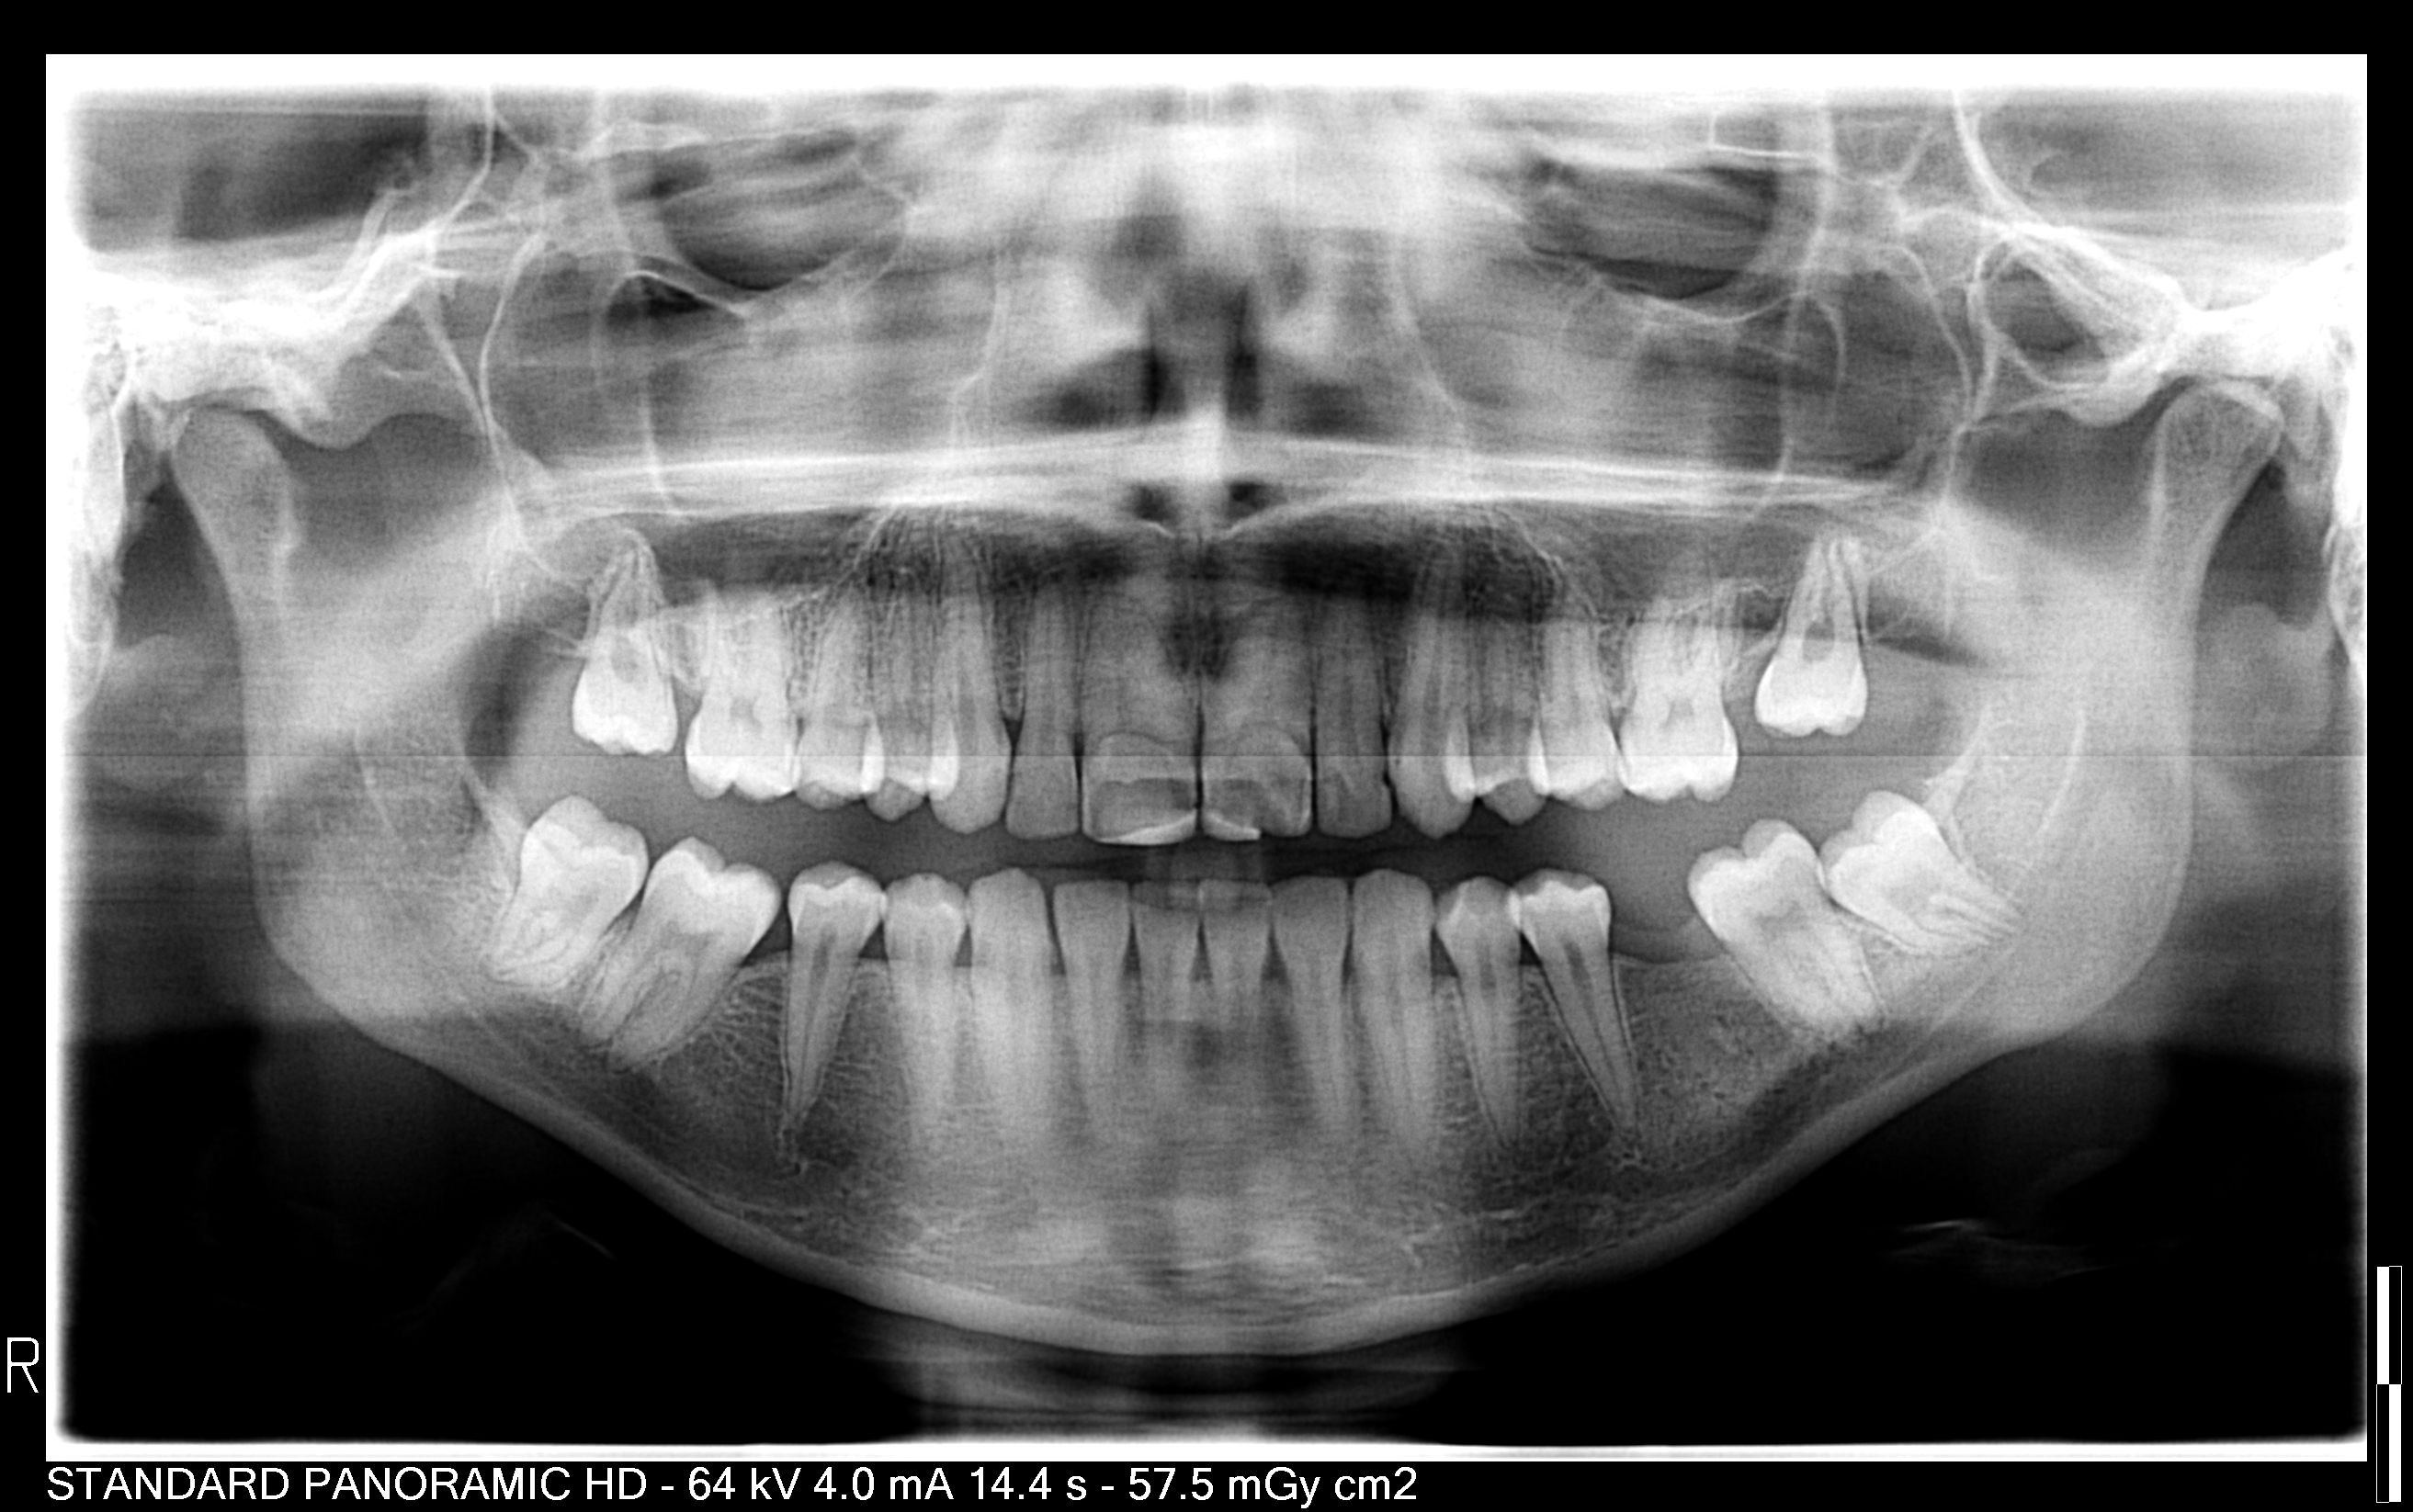

Deze week gaan ze porseleinen facings plaatsen omdat mijn voortanden te groot zijn.

Weet u ook of dit de beste behandeling is? Want de tandarts is niet zeker of ze de tanden smaller kan maken met de facings omdat ze juist afgestuurd is aan haar esthetische opleiding. Ik zou ook volgens collega’s van haar tanden hebben dat minder dan 1% van de bevolking geeft,daarom dat dit zo moeilijk is.

In een tand zit een zenuw. Daar hangt het v af hoeveel smaller een facing gemaakt kan worden. De middenste tanden smaller de kleine snijtanden ernaast breder. De basis (wortel) wordt niet smaller. Wordt dat mooi. Kan haar terughoudendheid begrijpen. Als de tanden gaaf zijn zou ik dat bij mijzelf prefereren, dus niets doen. Men kent u zoals u nu bent ...waarom aan sleutelen, accepteer hoe mooi u bent.